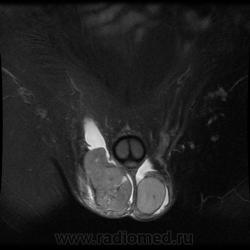

"Мужчина, 60 лет. Около 3 месяцев назад появился дискомфорт в области мошонки, увеличение правого яичка."

Считаю, что семинома - не самый вероятный вариант, т.к. структура опухоли достаточно неоднородная, есть распространение на придаток и границы четкие.

Могу предположить, неоплазию правого яичка.

Я в заключении вынес на первый ряд карциному яичка.